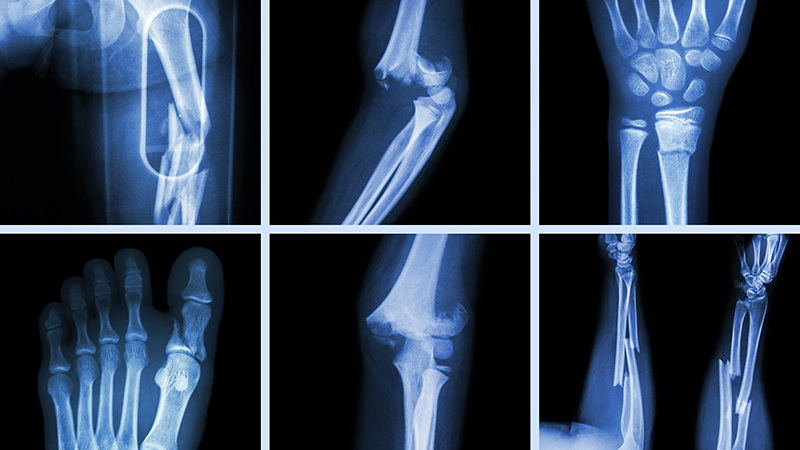

Kỹ thuật chụp X-quang xương đùi là phương pháp chẩn đoán hình ảnh dùng tia X để tạo hình ảnh của xương đùi. Hình chụp X-quang là một trong những công cụ quan trọng hỗ trợ bác sĩ xác định tình trạng của bệnh nhân. Bài viết dưới đây sẽ cung cấp cho bạn những thông tin hữu ích về phương pháp chụp X-quang xương đùi.

Chụp X-quang là một phương pháp chẩn đoán hình ảnh sử dụng tia X để ghi nhận hình ảnh mô và xương trong cơ thể. Tia X là một dạng bức xạ có năng lượng cao. Chùm tia X có thể dễ dàng xuyên qua các mô mềm và dịch trong cơ thể người và bị cản lại với các mô đặc như xương. Nếu mô có độ đậm đặc cao thì tia X sẽ khó xuyên qua hơn, đặc biệt là các mô đặc như xương. Nhờ vậy, hình ảnh được tạo ra giúp các bác sĩ quan sát và chẩn đoán bệnh chính xác.

Để xác định chính xác vị trí gãy xương, bác sĩ thường chỉ định chụp X-quang xương đùi, cung cấp hình ảnh tình trạng gãy xương, vị trí gãy và kiểu gãy xương cho bác sĩ nhanh chóng nhất.